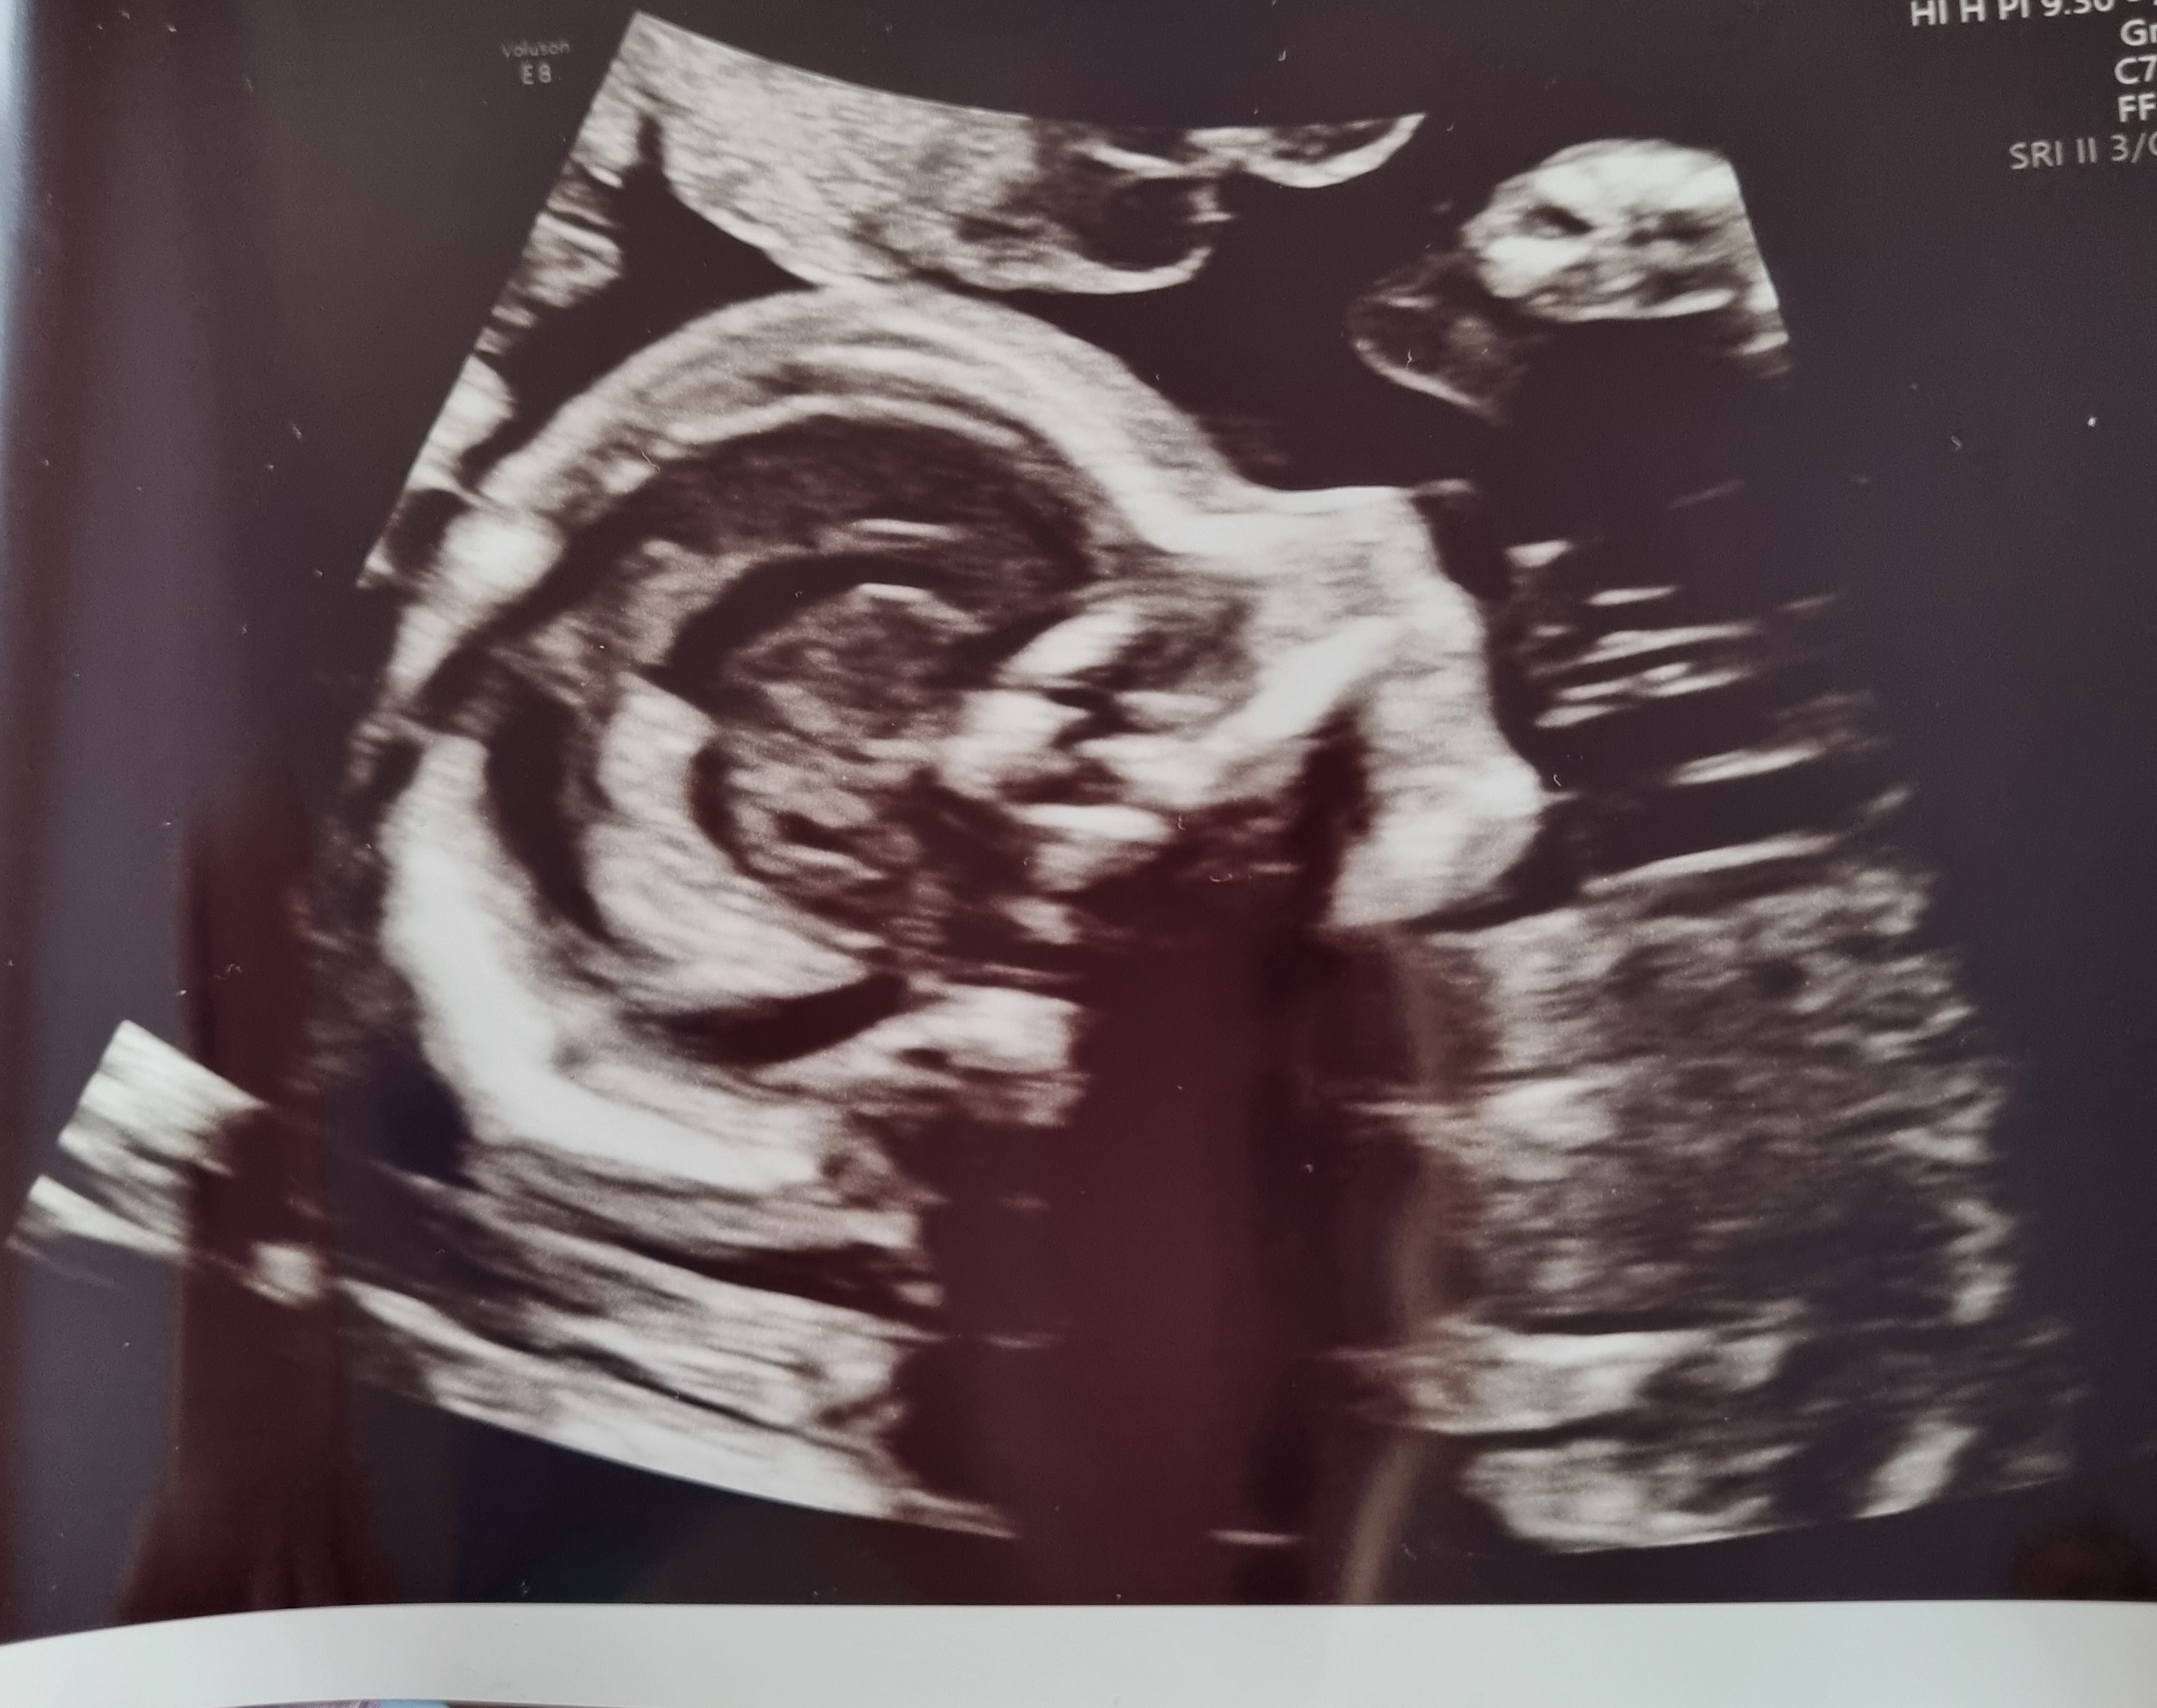

12+3 (målt til 12+5 idag)

Vi har en bebis perfektus på vei! Alt så helt perfekt ut, Lille var veldig aktiv, vinket, sprellet, strakk seg ut. Legen kalte den skihopper

Jeg kunne sett på den i evigheter, og vi fikk med oss ni bilder! Nå er alt verdt det. All kvalme, all smerte, all bekymring, alt er blåst vekk! Fin nakkefold, fin nese, ti små fingre, perfekte små armer og bein

Syns det er så rart å tenke på når man er på OTUL, at selve fosteret er kanskje rundt 8-10 cm - og på skjermen ser det ut som en ferdig baby. Trenger bare å vokse seg stor og sterk!